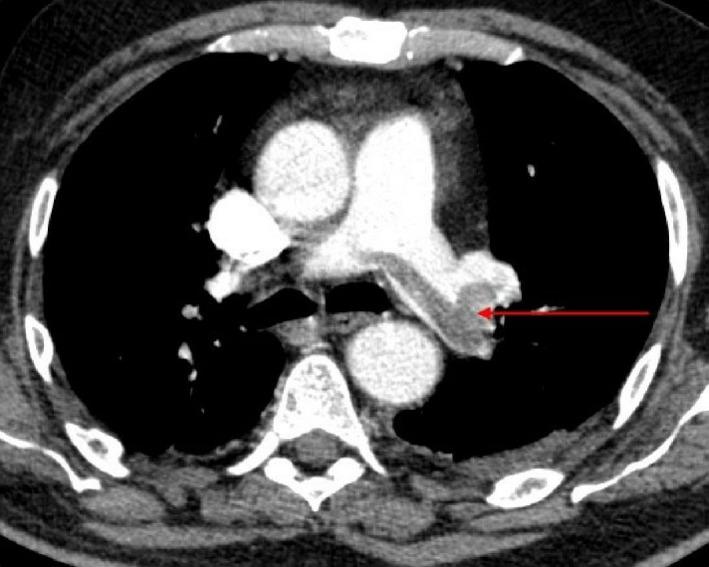

A clinical picture of pulmonary embolism revealing light-chain myeloma.

We are highlighting on the particularity of a clinical picture of pulmonary embolism revealing light-chain myeloma in a 56-year-old male patient. Myeloma remains a rare affection. Even though its revelation through pulmonary embolism remains rare, it can be explained by hyperviscosity syndrome accompanying it.